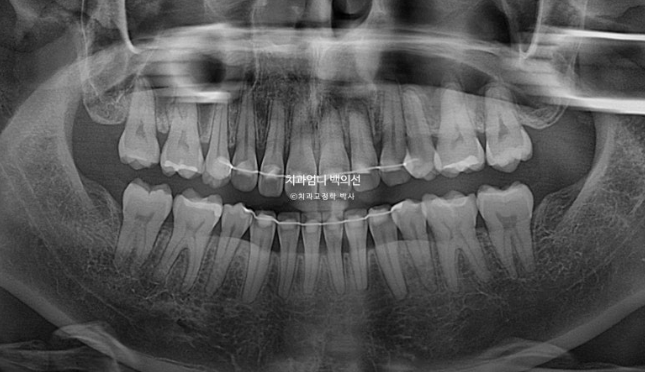

25.04

치근흡수는 없으며 치근평행도는 좋습니다.